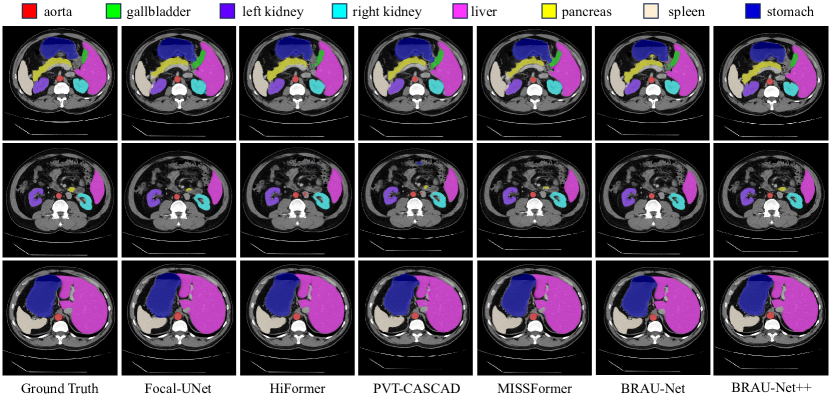

Some qualitative results of different methods on the Synapse dataset are given in Fig. 4. It can be seen from Fig. 4 that our method generates a smooth segmentation map for gallbladder, left kidney and pancreas, which demonstrate that the bi-level routing attention may excel at capturing the features of small targets, and the BRAU-Net++ can better learn both global and long-range semantic information, thus yielding better segmentation results.

Refer to caption

Figure 4: The segmentation results of different methods on the Synapse multi-organ CT dataset. Our BRAU-Net++ shows a relatively better visualization than other methods.